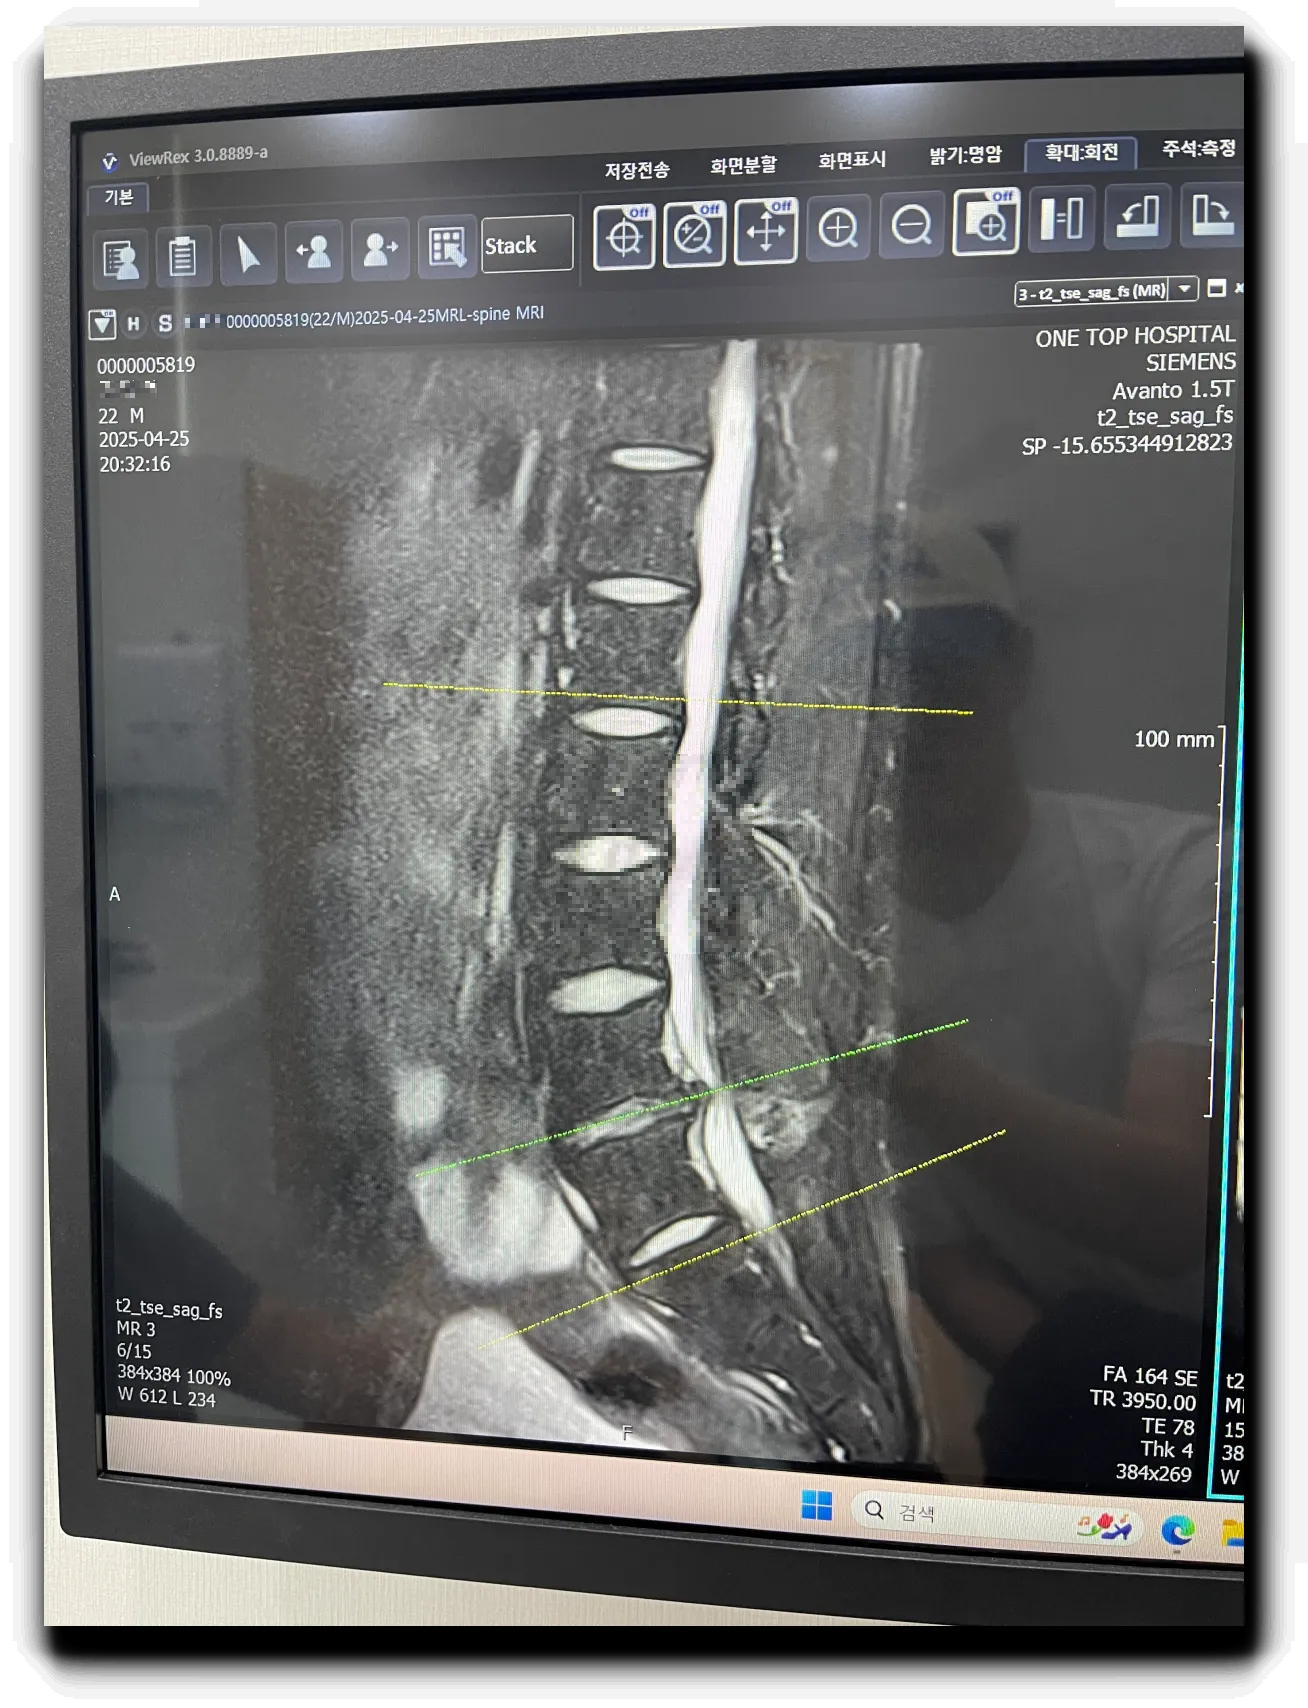

- 요추 4-5 사이가 많이 탈출해서 신경을 50% 이상 누르고 있다

- 요추 4-5 사이의 심한 탈출로 오른쪽 다리 방사통을 유발한다